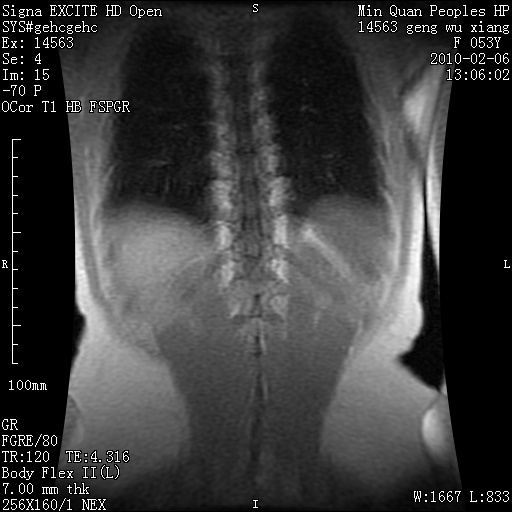

标题: MRI2762:胆道梗阻原因?

f,53y,全身黄染多日。

高位胆道梗阻 胆管癌可能性大

支持 高位胆道梗阻 胆管癌可能性大。